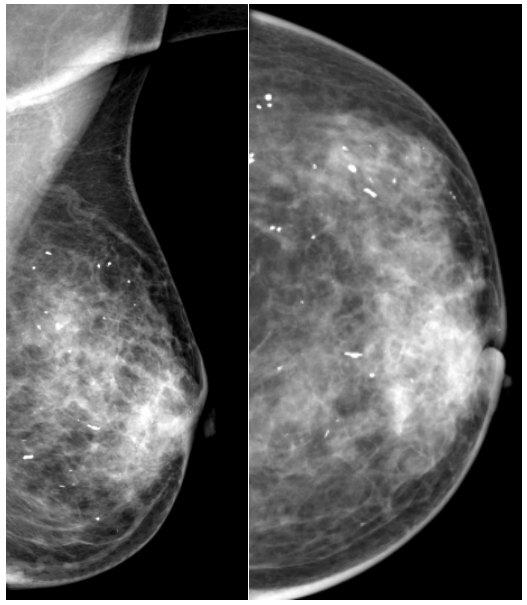

乳腺的良性钙化约占乳腺钙化的80%,恶性钙化常见于乳腺癌或其它肿瘤,约占乳腺钙化的20%。约30%-50%的乳腺癌患者在钼靶片上可显示微小的钙化。影像学主要从两个方面对乳腺钙化进行分析,即:钙化的形态和钙化的分布。良性钙化的“白点”往往表现为粗大的颗粒状(个头比较大,大“白点”)、边缘清楚、形状规则(圆形、卵圆形等),且呈散在分布。恶性钙化的“白点”往往表现为细小砂砾样(个头比较小,小“白点”)、边界模糊、形状不规则,呈一堆堆或一簇簇、一条条状的分布。

乳腺炎的良性钙化:粗大的颗粒状钙化,边界清晰,形状规则,呈散在分布。